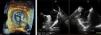

Transesophageal echocardiography performed 24 hours prior to the procedure showed no thrombus in the left appendage but revealed the presence of high-density spontaneous contrast (Figure 1). The LAA showed a 29 mm×26 mm entry orifice (Figure 2).